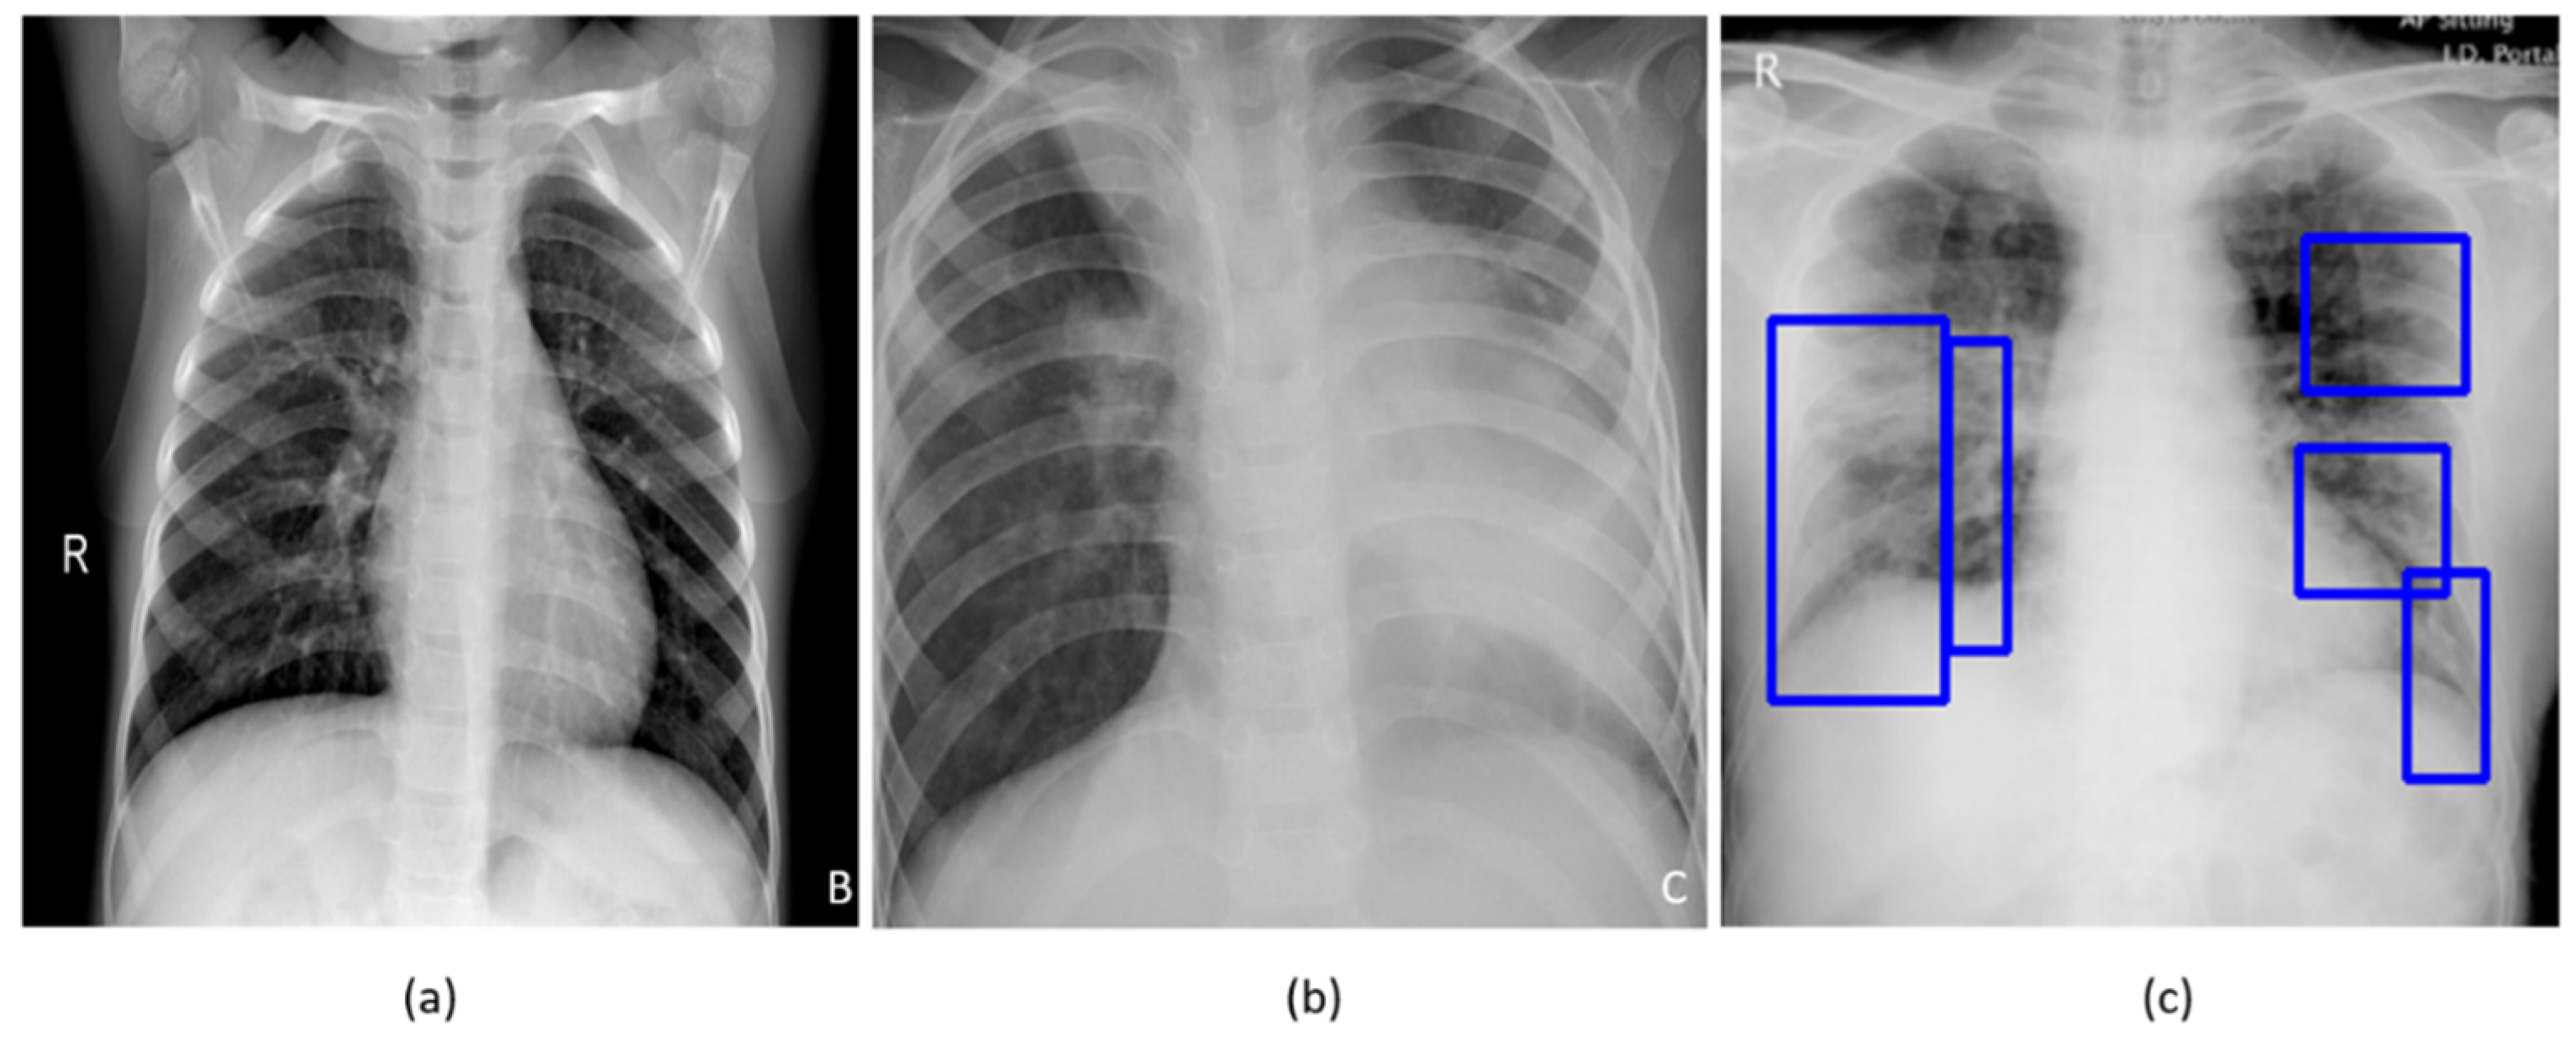

Confusion matrices for the results in Table 11 above are shown in Figure 7, while Figure 8 shows the learned behavior of the trained model. We observe that the learned interpretation is correctly focusing on the salient ROI, matching with the GT annotations that help to categorize COVID-19 CXRs as showing viral pneumonia. This is a significant improvement over the non-augmented training results shown in Figure 5.

Figure 8. Original CXRs, heat maps, and salient ROI visualization: (ac) show a sample Montreal-COVID-19 CXR with GT annotations, the corresponding heat map, and Grad-CAM visualization; (df) show a sample Twitter-COVID-19 CXR with GT annotations, the heat map, and its associated class activation maps. Blue frames in (a,d) denote radiologist annotations indicating disease regions, which serve as ground truth in our analysis.